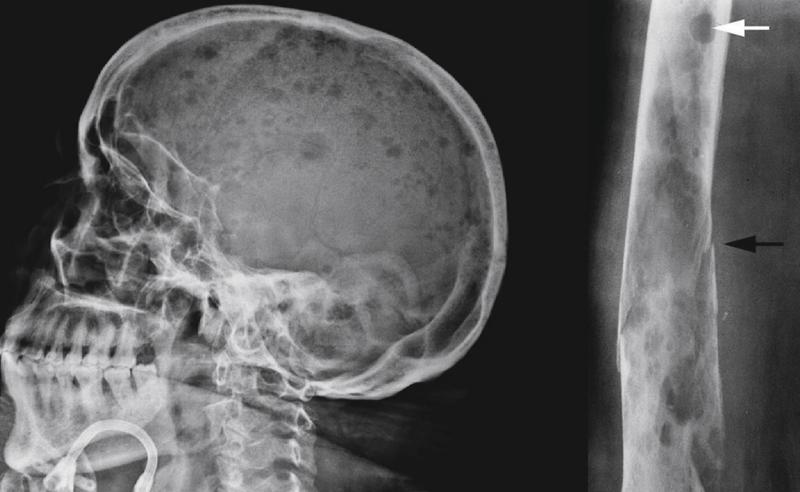

Los síntomas que presenta el cáncer de Mieloma Múltiple están las náuseas, dolor y/o fracturas en los huesos, principalmente en la columna vertebral y el pecho, recuentos bajos de células sanguíneas, pérdida del apetito, fatiga, entumecimiento o debilidad en las piernas, estreñimiento, sed excesiva, entre otros.